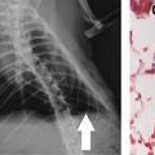

Científicos desarrollan un pulmón funcional en laboratorio

Un equipo de investigadores de la Universidad de Yale ha dado un nuevo paso en la creación de órganos de laboratorio al desarrollar un pulmón funcional. Al implantarlo en ratas, los investigadores comprobaron que los nuevos pulmones facilitaban el intercambio gaseoso, el proceso por el cual la sangre recibe oxígeno desde el aire y se desprende de anhídrido carbónico. Este intercambio es la principal función de los pulmones y se produce en los alveolos. Los detalles de este experimento se publican en la revista «Science».